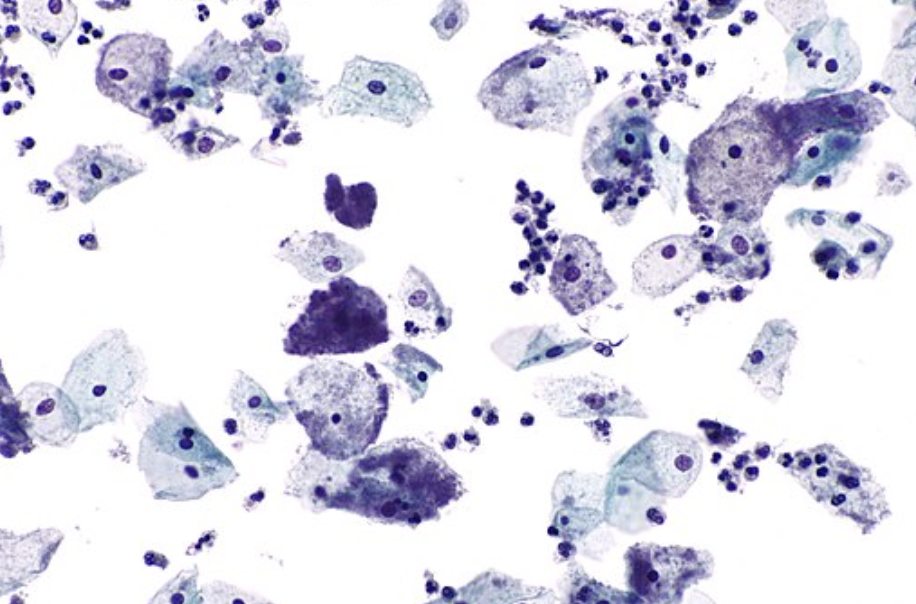

Figure: Clue cells - pap test. Wikimedia Commons. Published January 6, 2011. Image used under the Creative Commons Attribution-Share Alike 3.0 Unported license.

Testing for all patients with presentations suspicious of PID should include a pregnancy test first to rule out ectopic pregnancy. Additional labs include urinalysis, CBC with differential, and liver function studies (if Fitz-Hugh–Curtis syndrome is suspected). The most appropriate testing for Neisseria gonorrhoeae and Chlamydia trachomatis is by nucleic acid amplification and hybridization techniques, such as polymerase chain reaction (PCR) or DNA probes. These tests are more sensitive than culture, can be performed on cervical secretions or urine, and have a more rapid turnaround time. Microscopic evaluation of vaginal discharge is also available for bacterial vaginosis and trichomoniasis. A gram stain of cervical secretions showing gram-negative intracellular diplococci is indicative of N. gonorrhoeae. Testing for other STIs, including HIV and syphilis, should also be considered. For patients with severe allergies to currently recommended antibiotics, cultures with sensitivity testing on cervical secretions may be necessary.